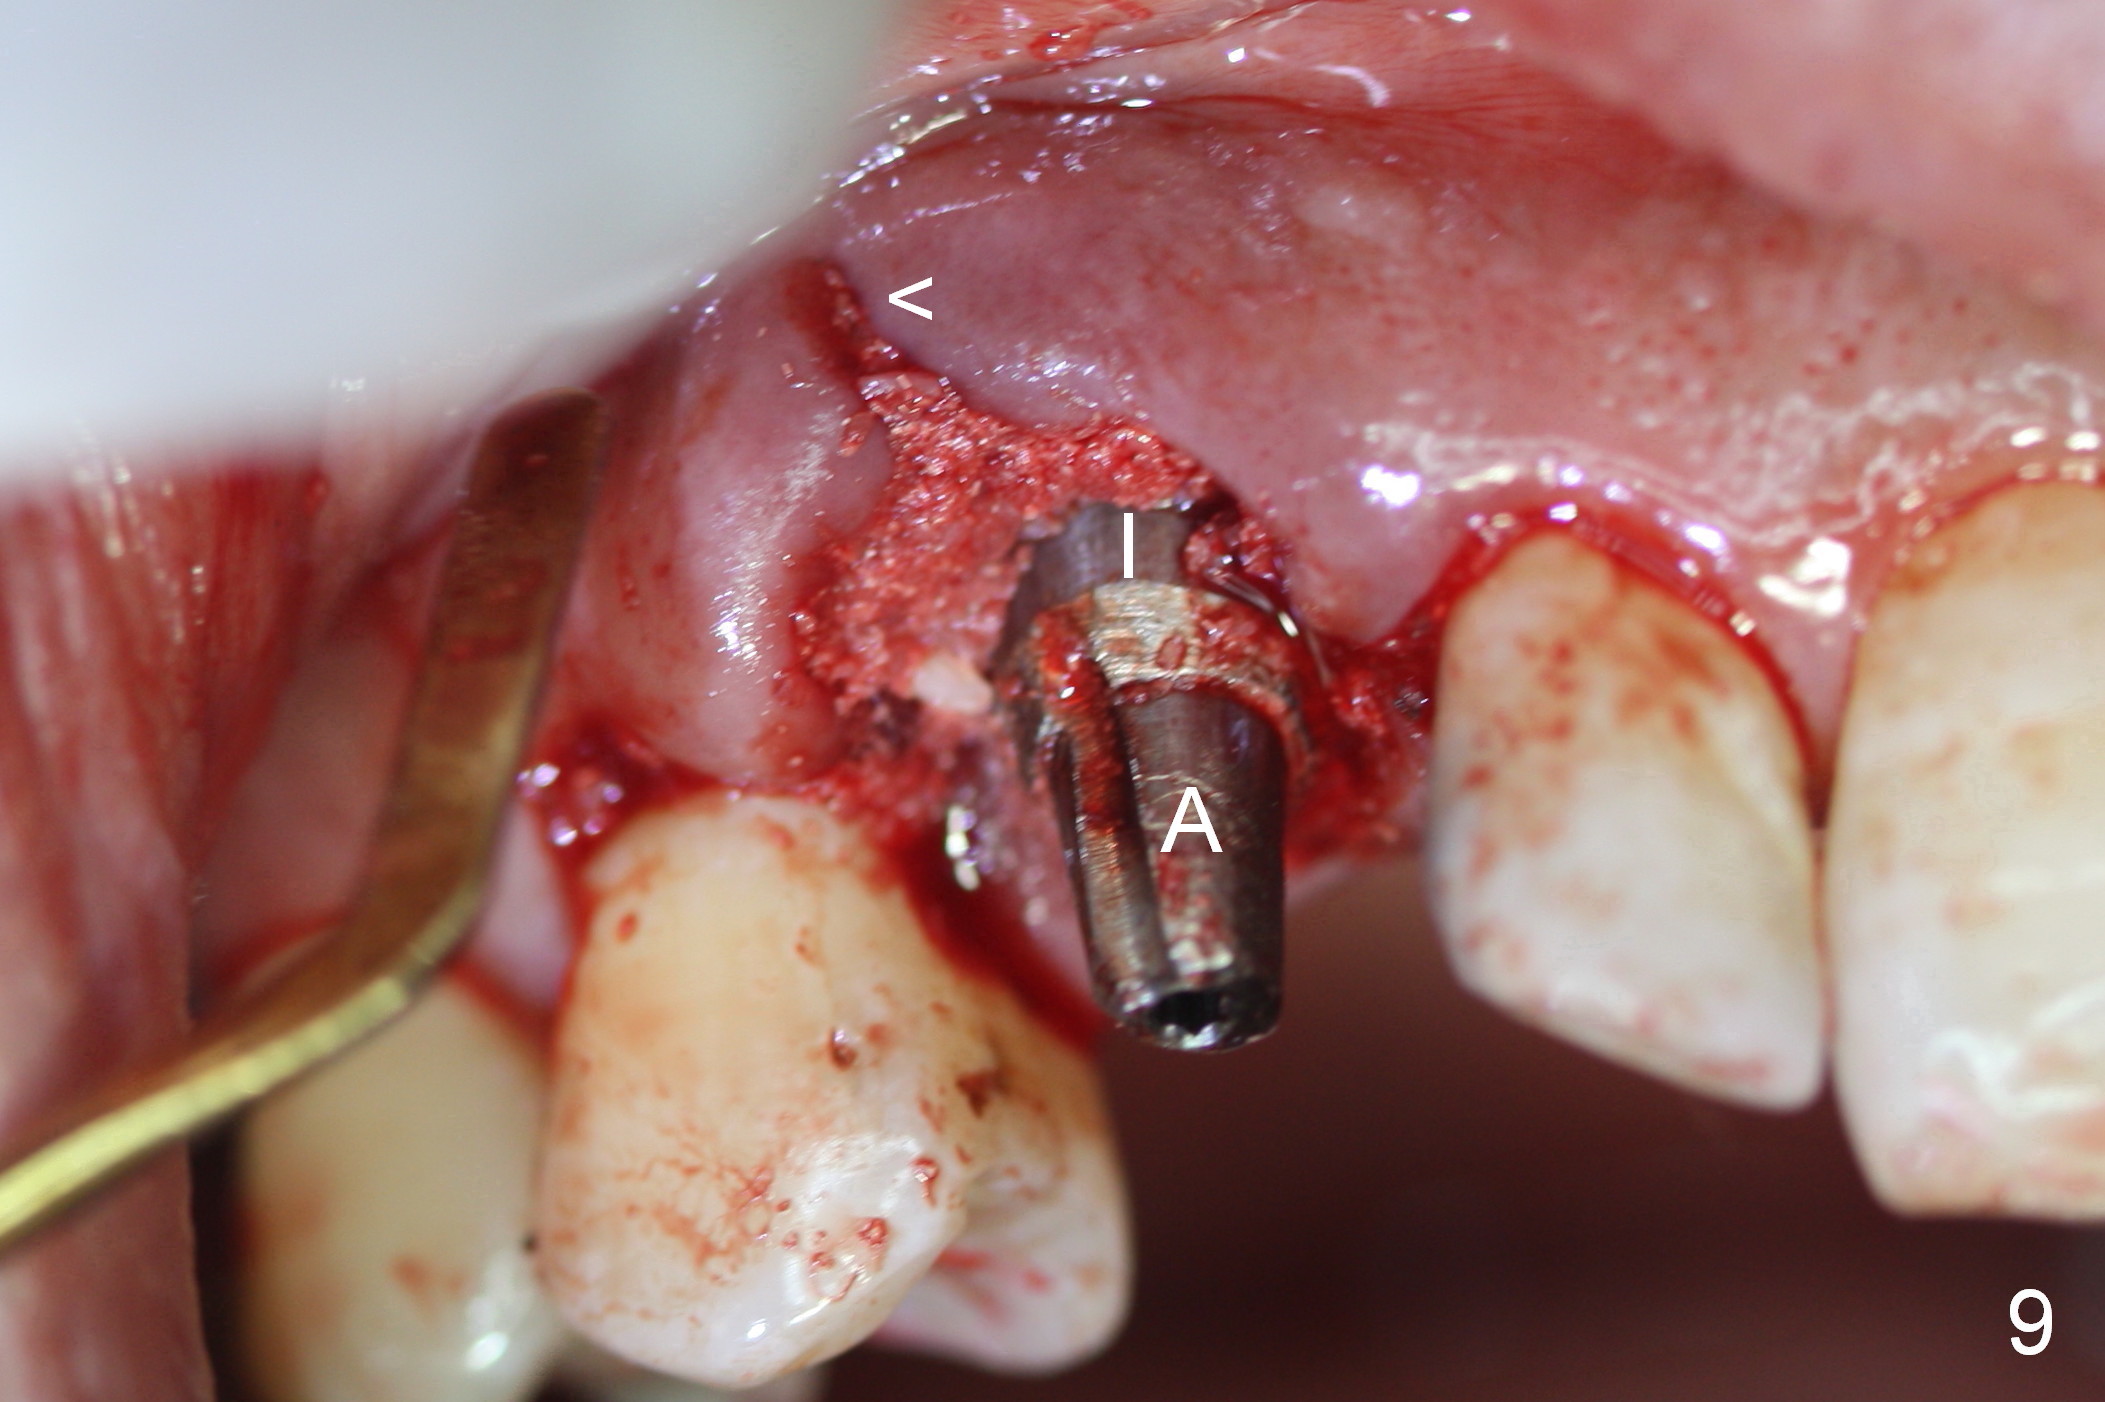

After 5x20 mm implant is placed, the distal gap is filled with bone graft (Fig.5 *). An abutment is placed (A) for fabrication of an immediate provisional (Fig.6 P). The latter hold the labial gingiva bulging (Fig.6 >). When the provisional is removed for bone grafting, the labial gingiva collapses (Fig.7 arrowheads). In fact a piece of cone-shaped Osteotape (Impladent) is placed palatal to the labial gingiva/thin labial plate and a small amount of graft is placed in the deepest area of the socket (labial to the osteotomy) prior to placement of the implant. More graft is placed in the peri-implant gap, particularly labially to keep the labial gingiva convex (Fig.8 arrowheads). The lacerated gingiva is to be approximated with perio glue (Fig.9 <). Collagen dressing is placed over the exposed graft before cementation of the provisional. Perio dressing is applied for further protection and seal.